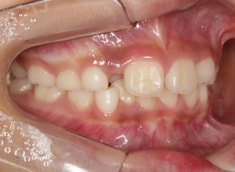

治療中